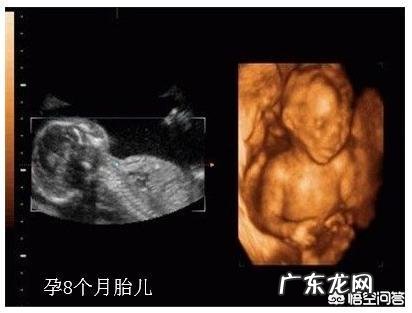

怀孕8个月时,胎儿是怎么样的?孕8个月已经进入孕晚期,这一时期孕妈妈最大的变化是“肚大如箩”,低头都无法看到自己的脚了,孕妈的体重增长达到了一个新阶段,说明胎宝宝的成长也进入到一个关键时期 。

身长为41-45厘米,体重1600-1800克,胎宝宝身体的主要器官已经发育完毕;

怀孕8个月,胎儿体重是1800克,胎儿头臀长是43.6厘米,双顶径是 8.16厘米,腹围26厘米,股骨长 6.42厘米 。

胎儿的皮下脂肪增多,肺部和肠道发育接近成熟,胎儿的手指和脚趾甲发育完善,这时期是胎动的活跃期,胎儿生长发育的高峰期 。

怀孕8个月最后一周是32周,这的时候胎儿的身高约40~44厘米,股骨长约6.43厘米,双顶径约8.17厘米,体重约1700~1900克 。